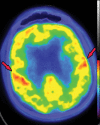

Neurodegenerative diseases are a devastating group of disorders that can be difficult to accurately diagnose. Although these disorders are difficult to manage owing to relatively limited treatment options, an early and correct diagnosis can help with managing symptoms and coping with the later stages of these disease processes. Both anatomic structural imaging and physiologic molecular imaging have evolved to a state in which these neurodegenerative processes can be identified relatively early with high accuracy. To determine the underlying disease, the radiologist should understand the different distributions and pathophysiologic processes involved. High-spatial-resolution MRI allows detection of subtle morphologic changes, as well as potential complications and alternate diagnoses, while molecular imaging allows visualization of altered function or abnormal increased or decreased concentration of disease-specific markers. These methodologies are complementary. Appropriate workup and interpretation of diagnostic studies require an integrated, multimodality, multidisciplinary approach. This article reviews the protocols and findings at MRI and nuclear medicine imaging, including with the use of flurodeoxyglucose, amyloid tracers, and dopaminergic transporter imaging (ioflupane). The pathophysiology of some of the major neurodegenerative processes and their clinical presentations are also reviewed; this information is critical to understand how these imaging modalities work, and it aids in the integration of clinical data to help synthesize a final diagnosis. Radiologists and nuclear medicine physicians aiming to include the evaluation of neurodegenerative diseases in their practice should be aware of and familiar with the multiple imaging modalities available and how using these modalities is essential in the multidisciplinary management of patients with neurodegenerative diseases.©RSNA, 2020.